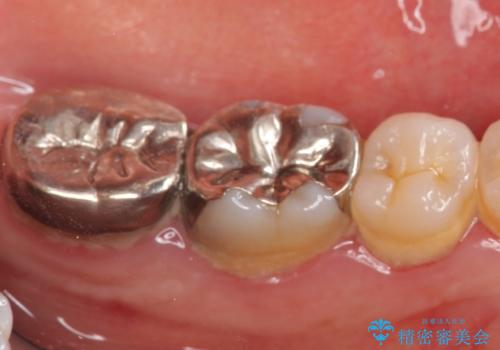

歯周外科手術終了後、歯茎の回復を待ち左下6、7ともにオールセラミッククラウン(スタンダード)による補綴を行いました。

今回用いたオールセラミッククラウンはジルコニアフレームという白い素材の上にセラミックを盛っているため、審美性が非常に高いのが特徴です。

また、ジルコニアは人工ダイヤモンドの材料にも使われているほど高い強度を持っており、そのためオールセラミッククラウンは審美性だけでなく、奥歯やブリッジの補綴も可能とするクラウンです。